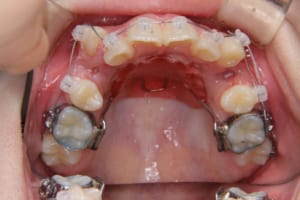

治療中

| 使用した装置 | 子どもの矯正治療(前期治療) 緩徐拡大装置 マルチブラケット装置 大人の矯正治療(後期治療/成人矯正治療) マルチブラケット装置 デーモンブラケット シルバーワイヤー 歯科矯正用アンカースクリュー(2本) ホールディングアーチ トランスパラタルアーチ |